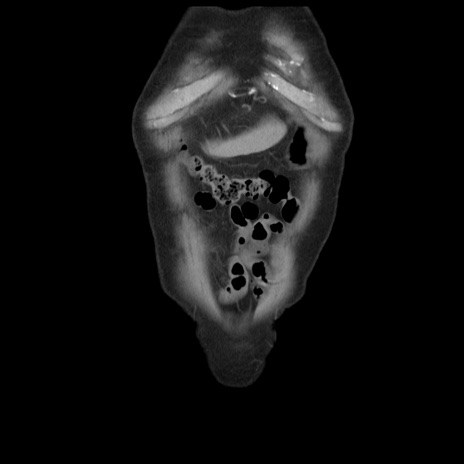

症例21(冠状断像)

【症例】70歳代男性

【主訴】腹痛

【現病歴】肝硬変・肝細胞癌にてかかりつけの方。約9時間前に食後より腹痛出現。症状が徐々に増悪し、嘔吐出現したため来院。

【既往歴】肝硬変、肝細胞癌(RFA、TACE後)

【身体所見】意識清明、表情苦悶様、BT 36℃、BP 129/78mmHg、P 88bpm、SpO2 97%(RA)、右上腹部から心窩部にかけて圧痛あり、反跳痛なし、筋性防御あり。

【データ】WBC 5800、CRP 0.16